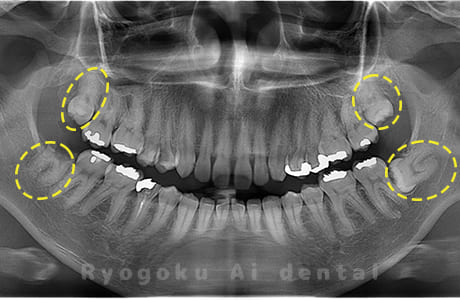

Case03

-

- 原因

- 上顎、下顎の親知らず

- 治療内容

- 上下4本の親知らずを抜歯したケースです。

<リスク・副作用>

手術後は痛み、腫れ、痺れなどの副作用が生じる場合があります。